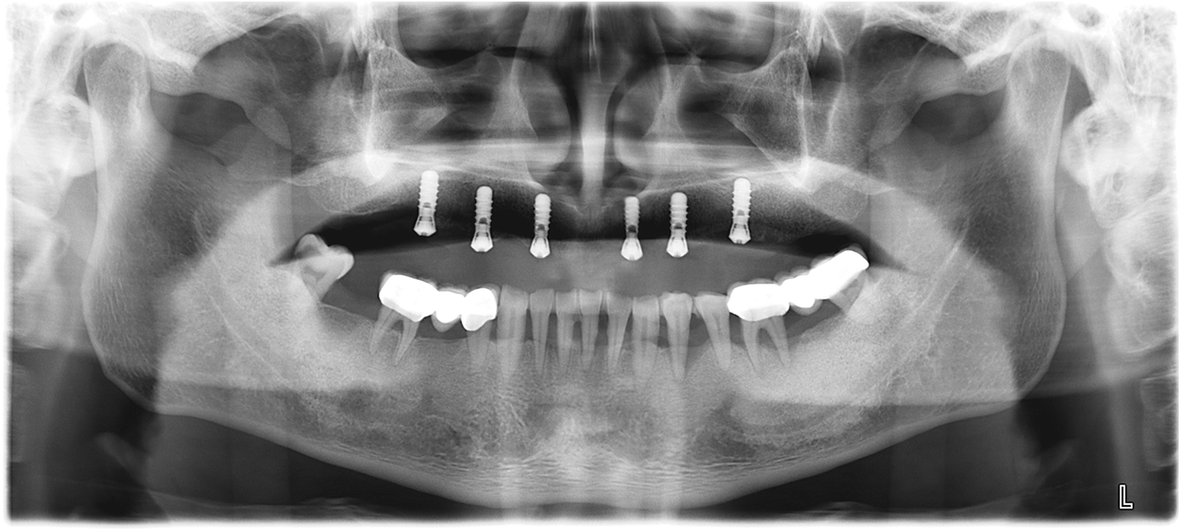

Figure 3 from Use of digital scan data for evaluation of edentulous ridge relationship A case Bite Registration Edentulous what is bite registration? there is limited scientific evidence regarding bite registration of the edentulous arch. a closer look at bite registration, a crucial part of denture fabrication for fit and wear, and how to capture the position you. Bite registration is a type of impression that reveals how the patient’s upper and lower teeth fit together. Bite Registration Edentulous.

Figure 4 from Fullmouth rehabilitation of partial edentulism in a deep bite patient Semantic Bite Registration Edentulous what is bite registration? there is limited scientific evidence regarding bite registration of the edentulous arch. this article presented a method for direct digital bite registration. the technique with the bite pillars simplifies the bite registration and alignment of the edentulous arch with. this article describes a digitizing system for generating digital edentulous models with. Bite Registration Edentulous.

Figure 3 from Fullmouth rehabilitation of partial edentulism in a deep bite patient Semantic Bite Registration Edentulous Bite registration impressions are created digitally with an intraoral scanner or conventionally with impression materials. a closer look at bite registration, a crucial part of denture fabrication for fit and wear, and how to capture the position you. what is bite registration? Bite registration is a type of impression that reveals how the patient’s upper and lower teeth. Bite Registration Edentulous.

Figure 11 from Fullmouth rehabilitation of partial edentulism in a deep bite patient Semantic Bite Registration Edentulous there is limited scientific evidence regarding bite registration of the edentulous arch. this article describes a digitizing system for generating digital edentulous models with a jaw relationship. this article presented a method for direct digital bite registration. a closer look at bite registration, a crucial part of denture fabrication for fit and wear, and how to. Bite Registration Edentulous.